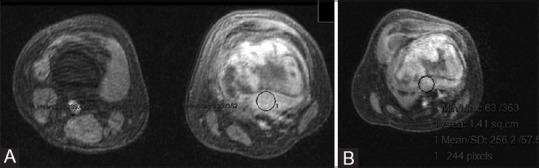

Our study included 14 patients (12 osteosarcomas and 2 malignant fibrous histiocytomas) with mean age of 21.8 years, treated with preoperative chemotherapy followed by surgery. They were evaluated with static and dynamic MRI twice, before starting chemotherapy and again prior to surgery. Change in tumor volume and slope of signal intensity - time curve were calculated and correlated with percentage of histological necrosis using Pearson correlation test.

The change in dynamic MRI slope was significant (P = 0.001). Also, ≥60% reduction in slope of the curve proved to be an indicator of good histological response [positive predictive value (PPV) =80%]. Change in tumor volume failed to show significant correlation (P = 0.071). Although it showed high negative predictive value (NPV = 85.7%), PPV was too low (PPV = 57.14%).

Dynamic MRI correctly predicts histological necrosis after administration of preoperative chemotherapy to bone sarcomas. Hence, it can be used as a preoperative indicator of response to neoadjuvant chemotherapy. On the other hand, volumetric assessment by static MRI is not an effective predictor of histological necrosis. This study proves the superiority of dynamic contrast-enhanced study over volumetric study by MRI.